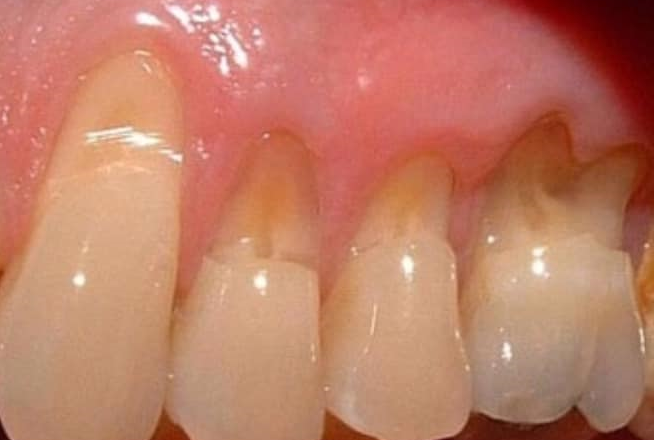

MÒN CỔ RĂNG - BIỆN PHÁP PHÒNG NGỪA VÀ XỬ TRÍ

Trong quá trình thăm khám bệnh tại Khoa Răng Miệng - Bệnh viện Đa khoa tỉnh Hải Dương, chúng tôi gặp một bệnh rất phổ biến, nhiều bệnh nhân mắc phải và đã được chúng tôi xử lý rất nhiều đó là: mòn cổ răng.